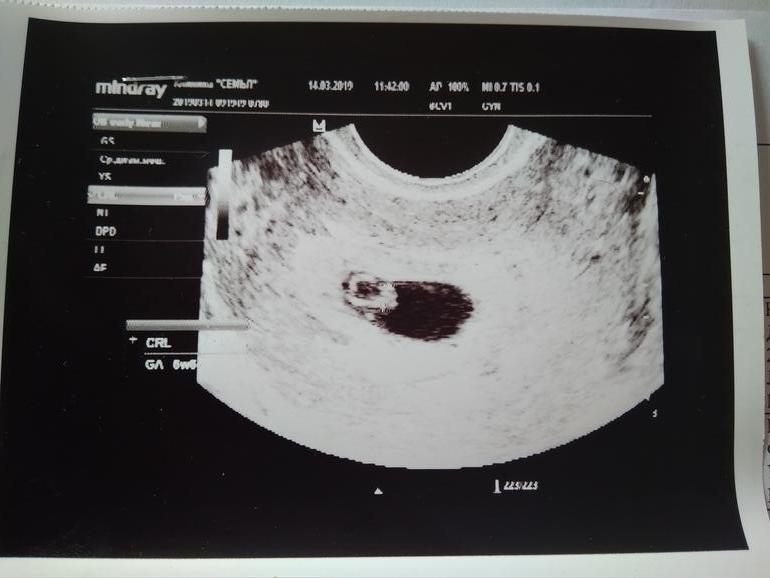

Итак, ровно 6 неделек. Что мы увидели? Плодное яйцо 30мм, желточный мешок 4мм и эмбриончик с КТР 2,9мм. Послушали сердечко 😍😍😍 ЖТ в правом яичнике 19мм.

Начала осмотр и удивленно говорит "ой, так тут уже эмбрион и даже сердцебиение! Включай скорее видео, я не хочу слишком долго смотреть".

Как сказала в конце УЗИ мой гинеколог "Всё хорошо". Поздравила меня с беременностью и спросила, что принимал мой муж, чтобы СГ улучшить. Ответ "только фолиевую кислоту" несколько её удивил (я для нее вообще одно сплошное удивление на протяжении всего наблюдения 😂), похвалила "Ну молодец он!"))

В заключении написала срок 4-5 недель, хотя при этом сказала, что по УЗИ поставила бы больше (5-6 недель). Я толком не поняла, почему она меньше указала срок (вроде как, чтобы меня рано врачи не загоняли). Ну да ладно, в любом случае на учет я пока не планирую вставать, не время еще. Гинеколог мне тоже посоветовала до 10 недель никуда не соваться, чтобы не лазили врачи, где не надо )))